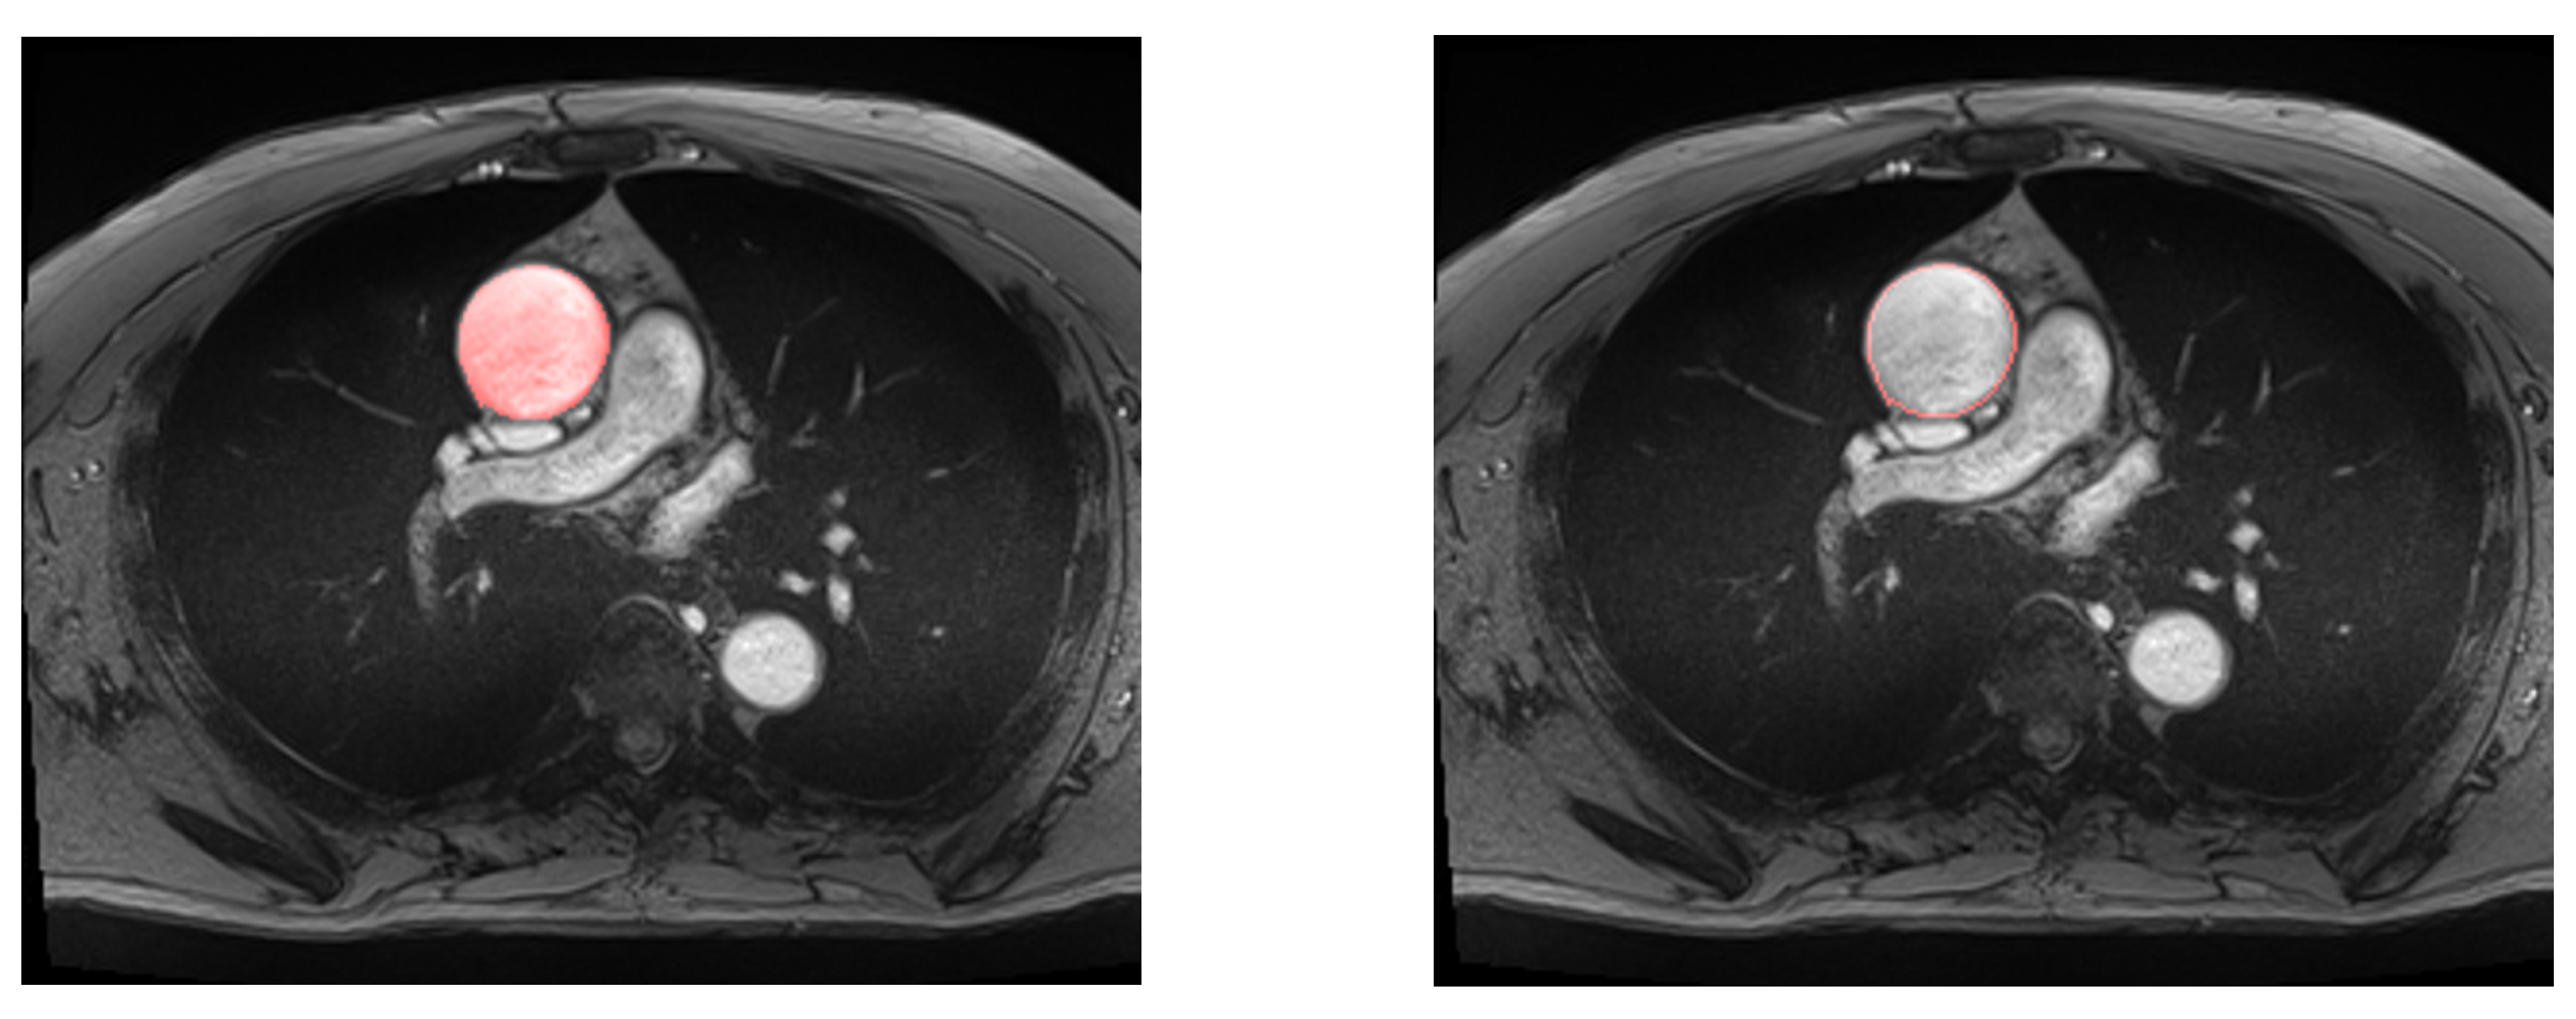

2.4. Deep Learning Segmentation and In-Vivo Elasticity Assessment

3.1. Evaluation of Deep Learning Models